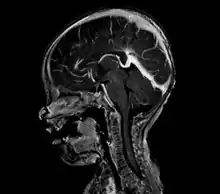

Large arteriovenous malformation of the parietal lobe | |

vein of Galen malformation

A cerebral AVM diagnosis is established by neuroimaging studies after a complete neurological and physical examination.[5][12] Three main techniques are used to visualize the brain and search for an AVM: computed tomography (CT), magnetic resonance imaging (MRI), and cerebral angiography.[12] A CT scan of the head is usually performed first when the subject is symptomatic. It can suggest the approximate site of the bleed.[3] MRI is more sensitive than CT in the diagnosis, and provides better information about the exact location of the malformation.[12] More detailed pictures of the tangle of blood vessels that compose an AVM can be obtained by using radioactive agents injected into the blood stream. If a CT is used in conjunction with an angiogram, this is called a computerized tomography angiogram; while, if MRI is used it is called magnetic resonance angiogram.[3][12] The best images of a cerebral AVM are obtained through cerebral angiography. This procedure involves using a catheter, threaded through an artery up to the head, to deliver a contrast agent into the AVM. As the contrast agent flows through the AVM structure, a sequence of X-ray images are obtained.[12]